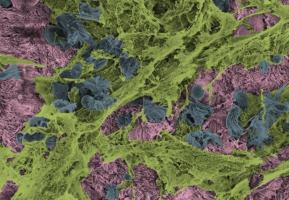

ALLERGIE : Ces cellules immunitaires inflammatoires qui survivent aux traitements